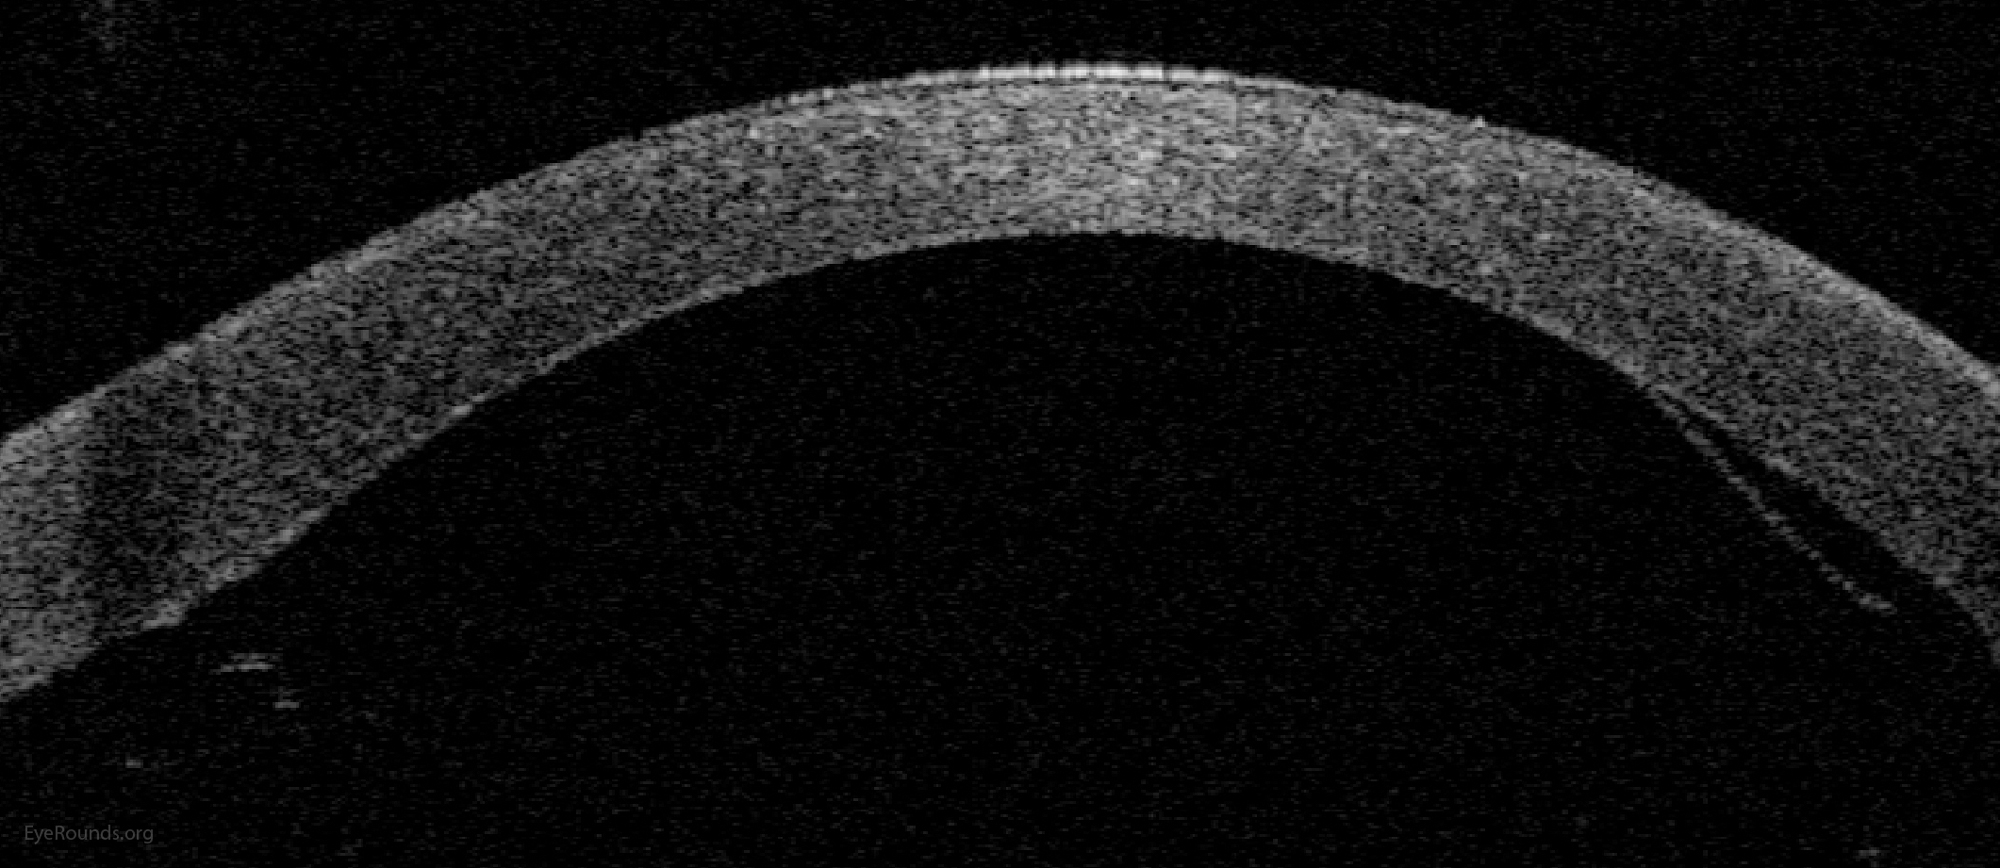

DMEK is a partial-thickness cornea transplant procedure that involves selective removal of the patient's Descemet membrane and endothelium, followed by transplantation of donor corneal endothelium and Descemet membrane without additional stromal tissue from the donor. The graft tissue is merely 10-15 microns thick. Similar to DSAEK, direct contact with the DMEK graft tissue should be avoided to prevent endothelial cell damage and graft failure. A clear corneal incision is created, the recipient endothelium and Descemet membrane are removed, and the graft is loaded into an inserter. After injecting the tissue into the anterior chamber, the surgeon orients and unscrolls the graft, and a bubble of 20% sulfur hexafluoride (SF6) is placed in the anterior chamber to support graft adherence (Figure 10). A variation known as Descemet membrane automated endothelial keratoplasty (DMAEK) utilized an automated preparation of the donor tissue that left a rim of donor stroma peripherally for easier tissue handling (Figure 11), but the procedure is no longer performed due to advances in DMEK that have allowed for easier insertion and manipulation of the graft tissue.

DMEK offers the most rapid visual rehabilitation of any keratoplasty technique to date (Figure 12). Final visual acuity can be outstanding due to minimal optical interface effects. Because less tissue is transplanted, there is a lower risk of allograft rejection and less long-term reliance on topical steroids compared with other types of keratoplasty. Discontinuation of topical steroids can be considered at or before 1 year after the procedure, especially for patients with elevated intraocular pressure.

Because of thinness, fragility, and its characteristic scrolling properties (with the endothelium facing outward), the donor tissue can be difficult to handle and contribute to technical difficulties with the procedure. There is a higher risk of graft edge lifts (Figure 13) compared with DSAEK, sometimes requiring a re-bubble procedure.